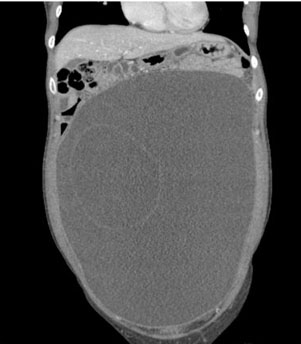

A 32-year-old nulliparous female presented to the emergency room reporting increasing abdominal fullness and discomfort. A computed tomography (CT) scan identified a 34 × 16 × 26-cm fluid filled cystic lesion likely arising from the left adnexa with a few thin septations (Figure 1 and Figure 2). There was mild ascites without peritoneal thickening or nodularity.

Figure 2: Coronal view of CT abdomen/pelvis with intravenous contrast demonstrating large 34 cm abdomino-pelvic cystic mass.